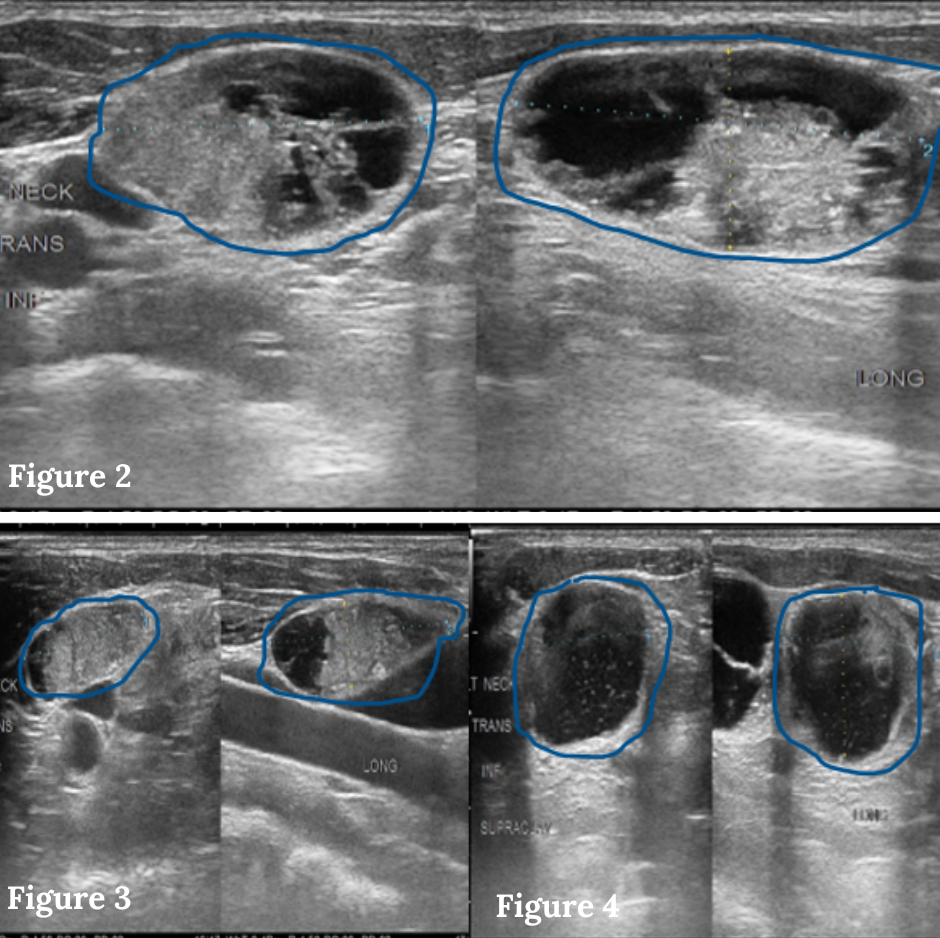

Figures 2-4: Ultrasound images of multiple enlarged, cancerous lymph nodes with a speckled, irregular appearance in the left side of the neck.